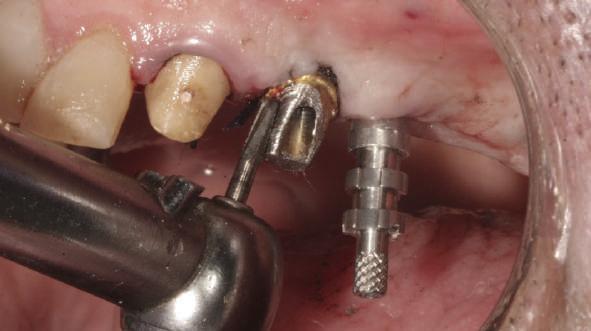

Reprepararea intraorală a bonturilor Acest pacient prezenta dentiţia maxilară compromisă, refuzând proteza mobilizabilă. Prin abordarea în etape, se menţin o parte din bonturile dentare naturale; s-a observat recesie în momentul amprentării pentru cel de-al doilea grup de implanturi.

Fig. 1 prezintă pacientul după inserarea primului set de bonturi implantare individualizate; dinţii naturali adiacenţi

sunt încă prezenţi pentru a susţine puntea provizorie.

Şapte luni mai târziu (fig. 2), acele bonturi individualizate din prima etapă au manifestat semne de recesie de 1-3mm. Atitudine: S-a decis reprepararea intraorală a tuturor bonturilor (fig. 3), astfel încât toate marginile bonturilor să fie la nivelul sau sub marginea gingivală (de notat că 1.1. şi 2.1. au fost submersaţi ulterior pentru a avea sprijin implantar deplin).

Deşi reprepararea a îmbunătăţit marcat estetica finală, a necesitat aplicarea şnurului de retracţie, amprente noi şi turnări noi.

Un caz separat dar similar ilustrează în figurile 4 și 5 reprepararea intraorală a bontului.

Cazul (1): Reprepararea intraorală a bonturilor Figurile

1. Aspect după inserarea primului set de bonturi implantare individualizate.

2. După 7 luni, bonturile individualizate din prima etapă au prezentat recesie de 1-3mm.

3. Bonturile repreparate intraoral.

Alt caz (1) Figurile

4. După osteointegrarea implantului 2.4., s-a observat recesia în etapa de amprentare a implantului 2.5.; s-a decis reprepararea marginilor bontului individualizat CAD/CAM 2.4. Înainte de preparare s-a aplicat şnur de retracţie pentru a evita lezarea ţesutului şi a îmbunătăţi vizibilitatea dintelui 2.3. şi a marginii bontului implantar individualizat. Aşa cum era de aşteptat, recesia a fost mai mare de-a lungul versantului distal al bontului 2.4. adiacent locului de extracţie vindecat/cu implantul mai nou.

5. Bontul individualizat aplicat (2.5.) cu bontul repreparat anterior (2.4.). Nu a survenit recesie nouă de o perioadă de peste 3 ani.